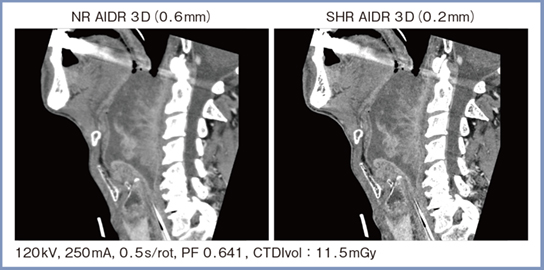

肺条件・NRモードの画像を見ると,十分に良好な画像が得られているが,MPR画像ではややボケが生じる。また,NRモード(スライス厚0.6mm)とSHRモード(スライス厚0.2mm)の画像を比較したところ,アキシャル画像ではそれほど画質に差を認めないが,スライス厚1mmのMPR画像では,SHRモードの方が病変がより明瞭であった(図2)。

図2 肺条件におけるNRモードとSHRモードの比較